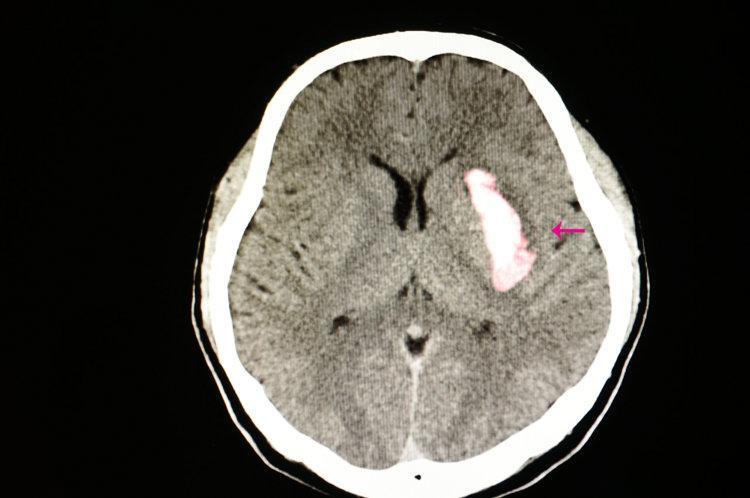

腦溢血又稱爲腦出血,臨牀上稱爲出血性腦卒中,屬於腦卒中中的一種。腦出血是指由非外傷性腦實質內血管破裂引發的出血,急性期病死率可高達30%—40%,即便是倖存者也多數會有不同程度的認知障礙、運動障礙、言語障礙等致殘後遺症。

腦出血的發生多與高血壓小動脈硬化的血管破裂有關,因此,臨牀上將此類腦出血稱爲高血他性腦出血。

上海藍十字腦科醫院神經外科學術副院長於耀宇指出,高血壓最嚴重的併發症之一就是高血壓腦出血,高血壓會導致顱內的小動脈呈現病理性變化,一旦患者情緒過於激動、劇烈運動等導致血壓出現劇烈波動,就會導致小動脈管破裂,血液進入腦室內或腦實質,從而導致腦出血。